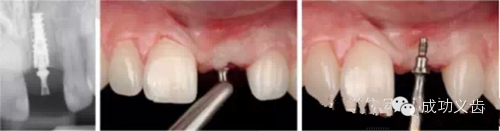

图3.即刻种植1,2008年的拔牙即刻种植病例,完美修复效果。

图4.即刻种植2,2013年复查。种植体周围骨组织稳定,龈乳头依然尖锐。颜色粉嫩,赏心悦目。